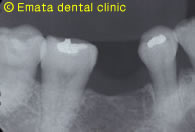

右下の奥歯が抜歯になりました。隣の歯は健康な歯なので削ってブリッジにすることを避けたいとの希望でした